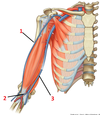

1? 2?

1: Teres major muscle

2: Latissimus dorsi muscle